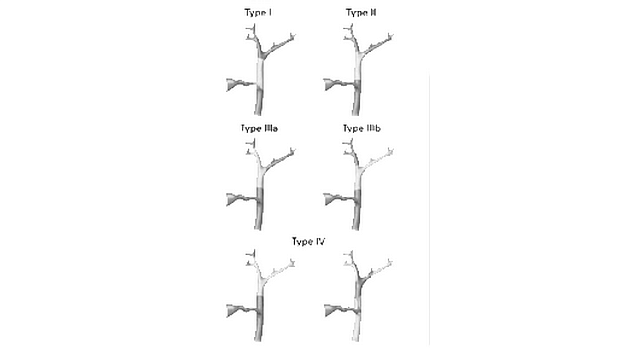

Рак билиарного тракта возникает с частотой примерно 7500 случаев в год, причем 5000 из них составляет рак желчного пузыря [7]. Классификация опухолей желчевыводящих путей по локализации представлена на рис. 5.